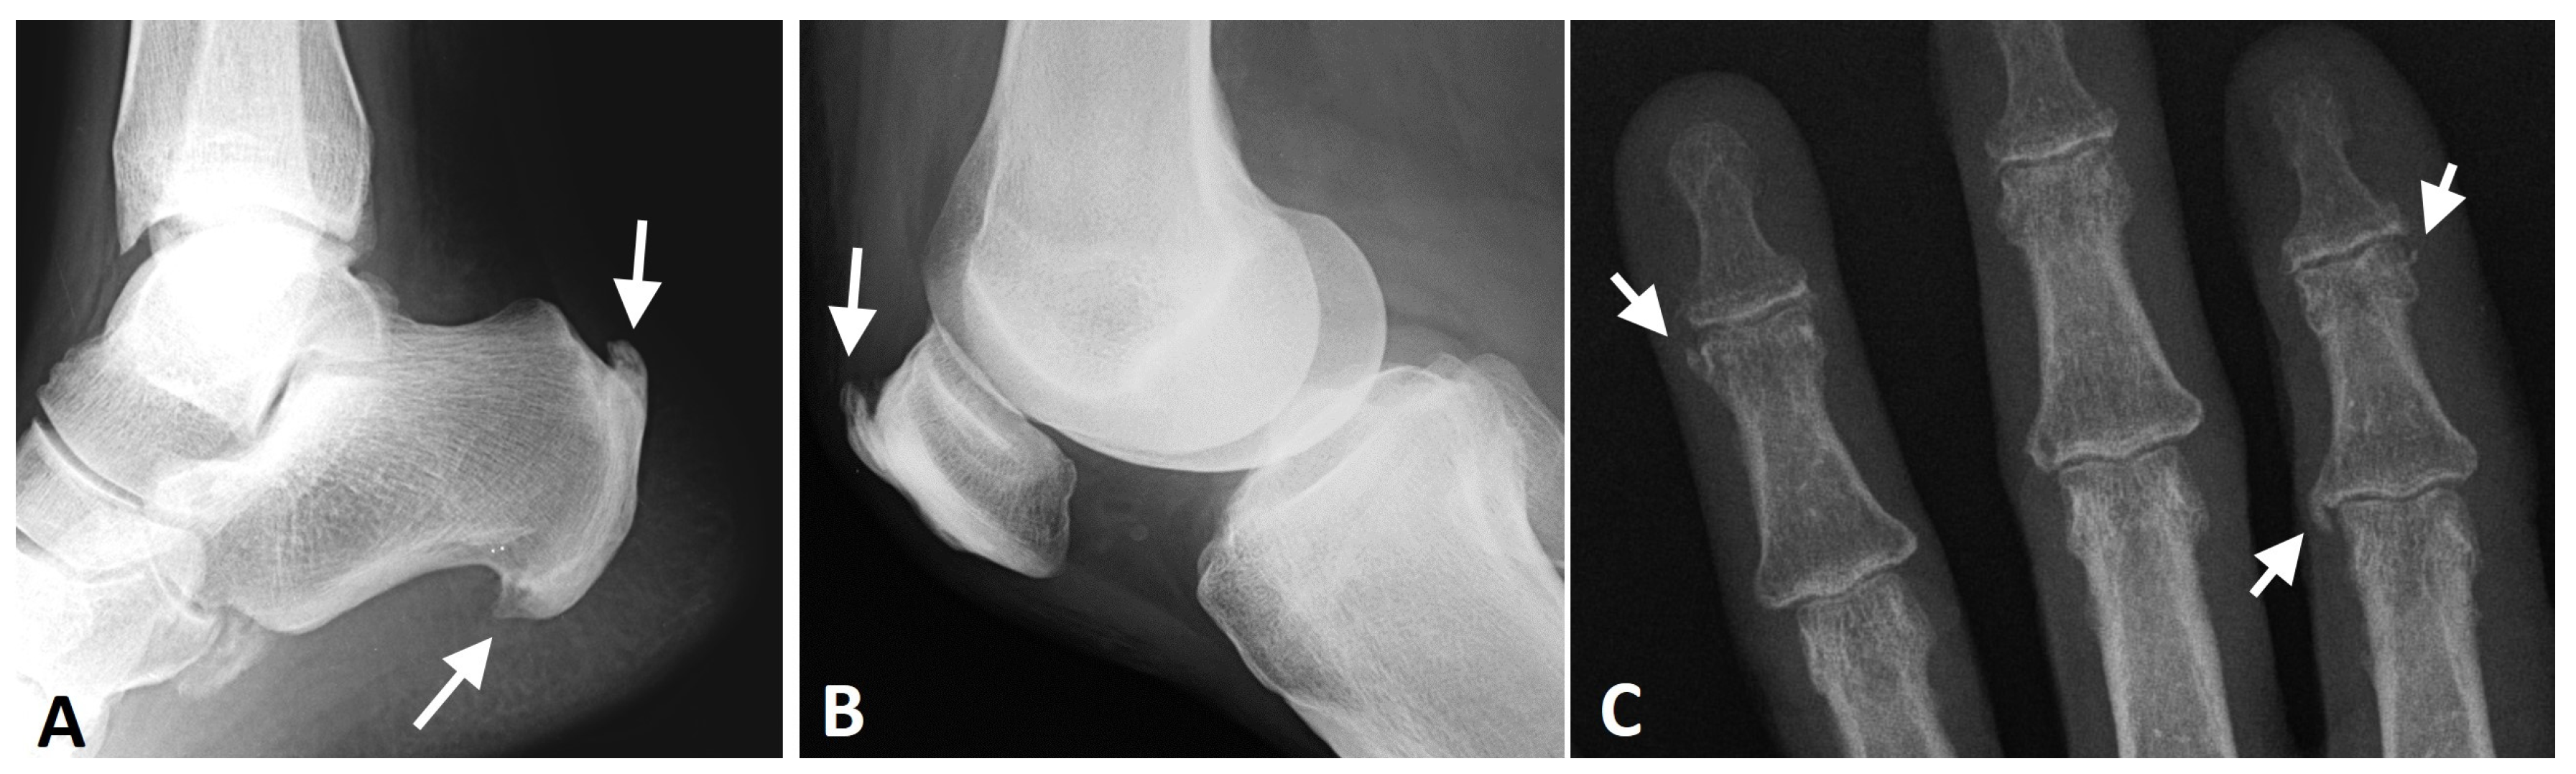

Appendicular DISH is characterized by the involvement of joints that are not commonly affected by primary osteoarthritis (e.g., elbows, shoulders, anterior chest wall, etc.) [32,78] as well as prominent, thick peripheral enthesopathies with calcification and ossification of extra-articular tendinous entheses such as in the tibial tuberosity, olecranon, and Achilles insertion (Figure 9) [79]. In addition, the affected joints in DISH show the exuberant new bone formation and para-articular osteophytes [66]. These changes may result in a reduced range of motion in the affected joints and potentially the subsequent development of degenerative changes [4,75,79].

Figure 9.

Radiographs of the ankle, knee, and hand of a patient with thoracic DISH (not shown). (A) Lateral radiograph of the ankle, showing coarse, thick enthesophytes in the attachment of the Achilles tendon and plantar fascia to the calcaneus (arrows). (B) Lateral knee radiograph showing thick, coarse enthesophytes (arrow) in the attachment of the quadriceps tendon to the patella. (C) AP radiograph of the fingers, showing enthesophytes in the medial side of the 2nd metacarpophalangeal joint and 4th distal interphalangeal joint and the lateral side of the 2nd distal interphalangeal joint (arrows).